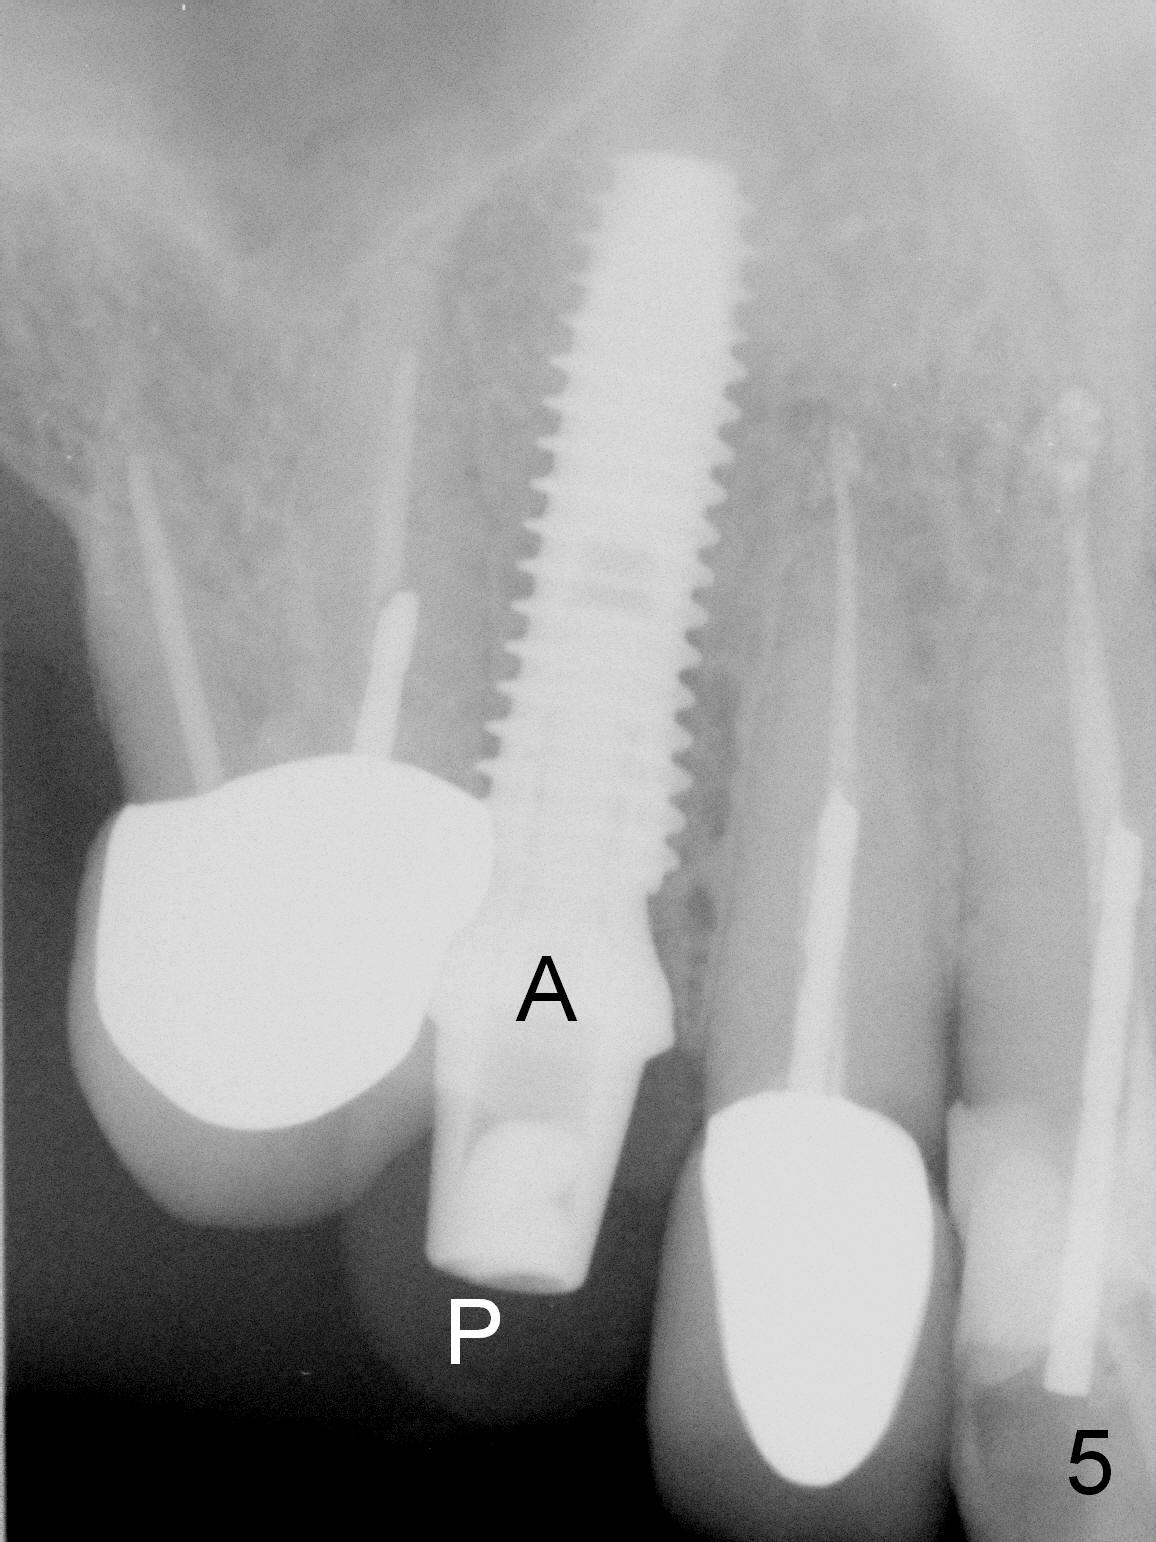

After extraction of the subgingival fractured upper right canine (Fig.1), the buccal plate is found to have been perforated at the apex. the root is measured 5x12 mm. Initial osteotomy with a 2 mm pilot drill shows that the bone is soft (Fig.2). After use of a 3.2 mm drill (underprep, normal drill size (3.7 mm)), a 4.5x15 mm implant is placed with insertion torque > 50 Ncm (Fig.3). The implant is further torqued until the implant plateau is 3 mm apical to the buccal gingival margin; a 5.5x5(3) mm abutment is placed (Fig.4,5 A). Osteogen plug is inserted into the apex of the socket, while the rest of gap is filled with mineralized cortical allograft and Osteogen. An immediate provisional (Fig.5,6 P) is fabricated to keep the graft in place, followed by periodontal dressing (Fig.6).

Three months postop, the provisional is dislodged (Fig.7-9). The mesial gingiva is hypertrophic buccally (Fig.8 *) and lingually (Fig.9 *). There appears to biologic width violation (Fig.5). The abutment should be changed to the one with smaller in diameter and longer in cuff (4.5x5(4) mm) with the buccal margin reduction.